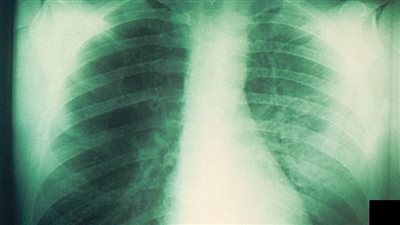

يعد سرطان الرئة واحد من أكثر أشكال السرطان فتكا، والتدخين هو أحد الأسباب الرئيسية للإصابة به، والعلاقة بين التدخين وسرطان الرئة موثقة جيدا مع كون التدخين مسؤولا عن غالبية حالات سرطان الرئة في جميع أنحاء العالم، إذ يحتوي التبغ على أكثر من 7000 مادة كيميائية، وكثير منها سام و70 مادة على الأقل تعرف باسم المواد المسرطنة.

وبحسب ما نشر في موقع تايمز أوف إنديا، هذه المواد تلحق الضرر بالخلايا المبطنة للرئتين، وعند استنشاقها، تدخل هذه المواد الكيميائية الرئتين وتسبب ضررا مباشرا لأنسجة الرئة، ويحدث هذا الضرر بطرق مختلفة، والتي نستعرضها فيما يلي.